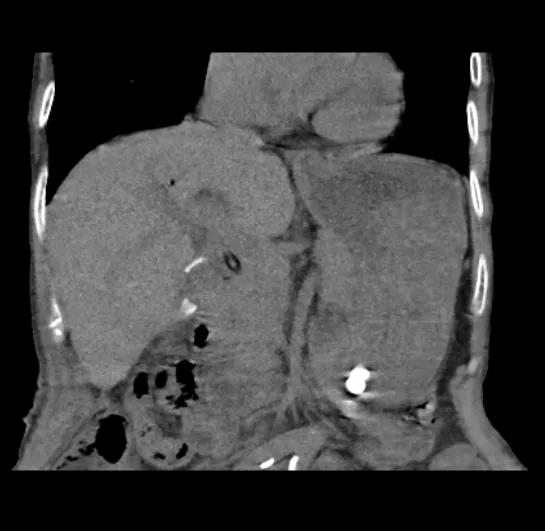

胆总管结石及肝内胆管多发结石(术前)

术中我科应用腹腔镜+硬质胆道镜经胆总管碎取胆总管结石及肝内胆管结石。

术后结石清除,胆管扩张减轻

术中一次性取净胆道结石,避免了结石残留,大大降低了短期内结石梗阻的复发几率,从而避免了再次手术的创伤打击,真正达到了微创手术的目的。